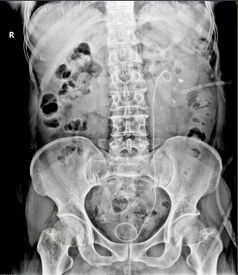

泌尿系统B超检查是一种利用超声波技术对人体泌尿系统进行无创性检查的方法。通过B超检查,医生可以观察到肾脏、输尿管、膀胱、前列腺等器官的形态、大小、位置以及内部结构,从而发现是否存在异常情况。

疑似泌尿系统疾病,如肾结石、肾积水、肾肿瘤、膀胱肿瘤等。